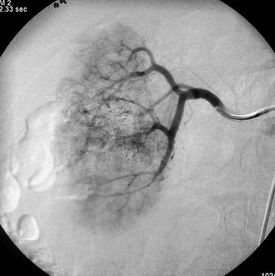

Obrázek 4 - angiografie ledviny po léčbě, bez známek přítomnosti patol. vakularizace

Následuje selektivní zavedení katétru či mikrokatétru do hilu ledviny a aplikace embolizačního materiálu.

Samostatná paliativní embolizace lokálně pokročilého karcinomu ledviny jako samostatná metoda nevede dle literárních údajů k prodloužení přežití pacientů. Na relativně malých souborech takto léčených pacientů je však popisovaná relativně dobrá tolerance výkonu a hlavně ve většině případů ústup či minimalizace symptomů onemocnění.